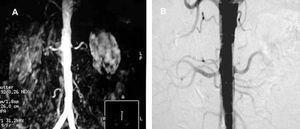

Contrast-enhanced computed tomography (CT angiography) provides high-resolution images and the possibility of 3-dimensional reconstruction. It is the technique of choice in the diagnosis and the preoperative study. The aortoiliac anatomy, the characteristics of the wall (inflammation, calcification, signs of rupture, thrombus), the visceral vessels and anatomical variations (horseshoe kidney, left renal vein, or left IVC) can be evaluated in detail (Figure 1). The disadvantages are the radiation and the use of a contrast agent. Contrast-enhanced magnetic resonance (MR) has the same properties as CT angiography, but eliminates the risk of nephrotoxicity and ionizing radiations (Figure 2). The degree of stenosis in visceral vessels may be overestimated, it does not detect calcifications and it produces artifacts in individuals with steel implants. However, in the follow-up of endoprostheses made of nitinol, MR angiography has been found to be useful in the detection of leaks.31-33

Figure 1. Axial images of abdominal aortic aneurysm and both iliac arteries (A and B). Detailed 3-dimensional reconstruction of the anatomy.

Figure 2. Image of an abdominal aortic aneurysm obtained with magnetic resonance angiography in a renal transplant recipient (right iliac artery). (Image courtesy of Dr I. García of Hospital Valdecilla, Santander, Spain.)